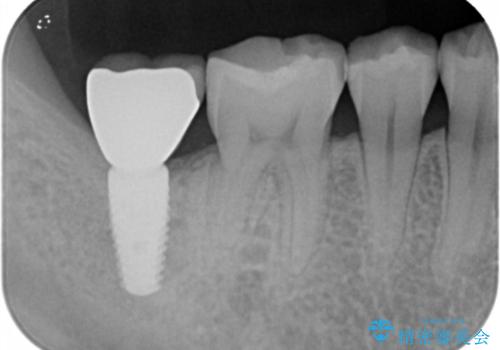

- フロスをすると引っかかる、食べ物がよく詰まるとのことで来院。

精査したところ詰め物が欠けており、物が挟まりやすく不潔になっていました。

また、小さめですが、虫歯になっていました。

そのままだといくら歯磨きを頑張っても虫歯が進行してしまいやすい状態となっていたため治療を勧めました。

虫歯を除去し、白くて目立たないセラミックインレーによる修復を行いました。

セラミックインレーの装着によりフロスが引っかからなくなりました。また、食べ物も詰まらなくなり、とても満足していただきました。